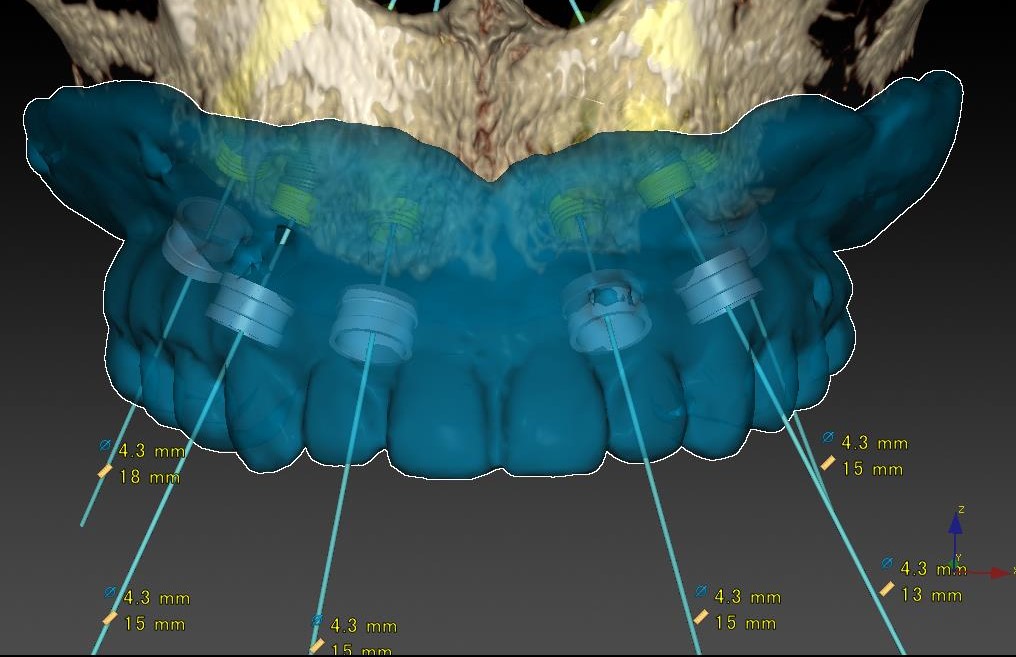

症例11

50代 男性 なんでも食べられるようになりたい

術前シミュレーション1

術前シミュレーション1

術前シミュレーション2

術前シミュレーション2

| 主訴 | 自分が一番元気に、何でも食べられる父親でいたい。家族との食事の時間が人生ですごく大切で、何とかしたい、と思っていた。 |

|---|---|

| 年代・性別 | 50代 男性 |

| 治療部位 | 上顎6~6 |

| 治療費用 |

インプラント手術料 |

| 手術回数 | 1回 |

| 治療期間 | 4ヶ月 |

| 手術時間 | 180分 |

| 治療回数 | 10回 |